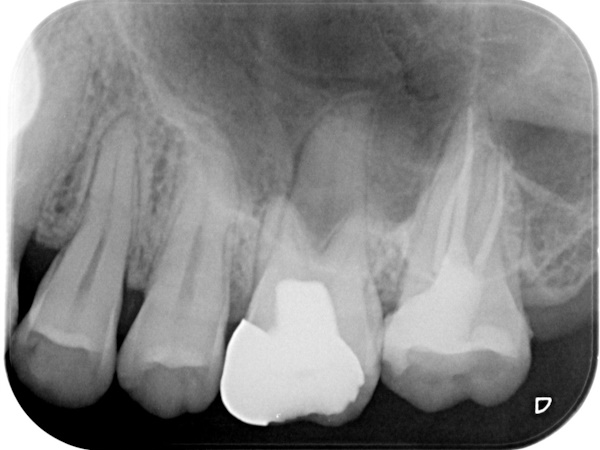

根管治療終了時